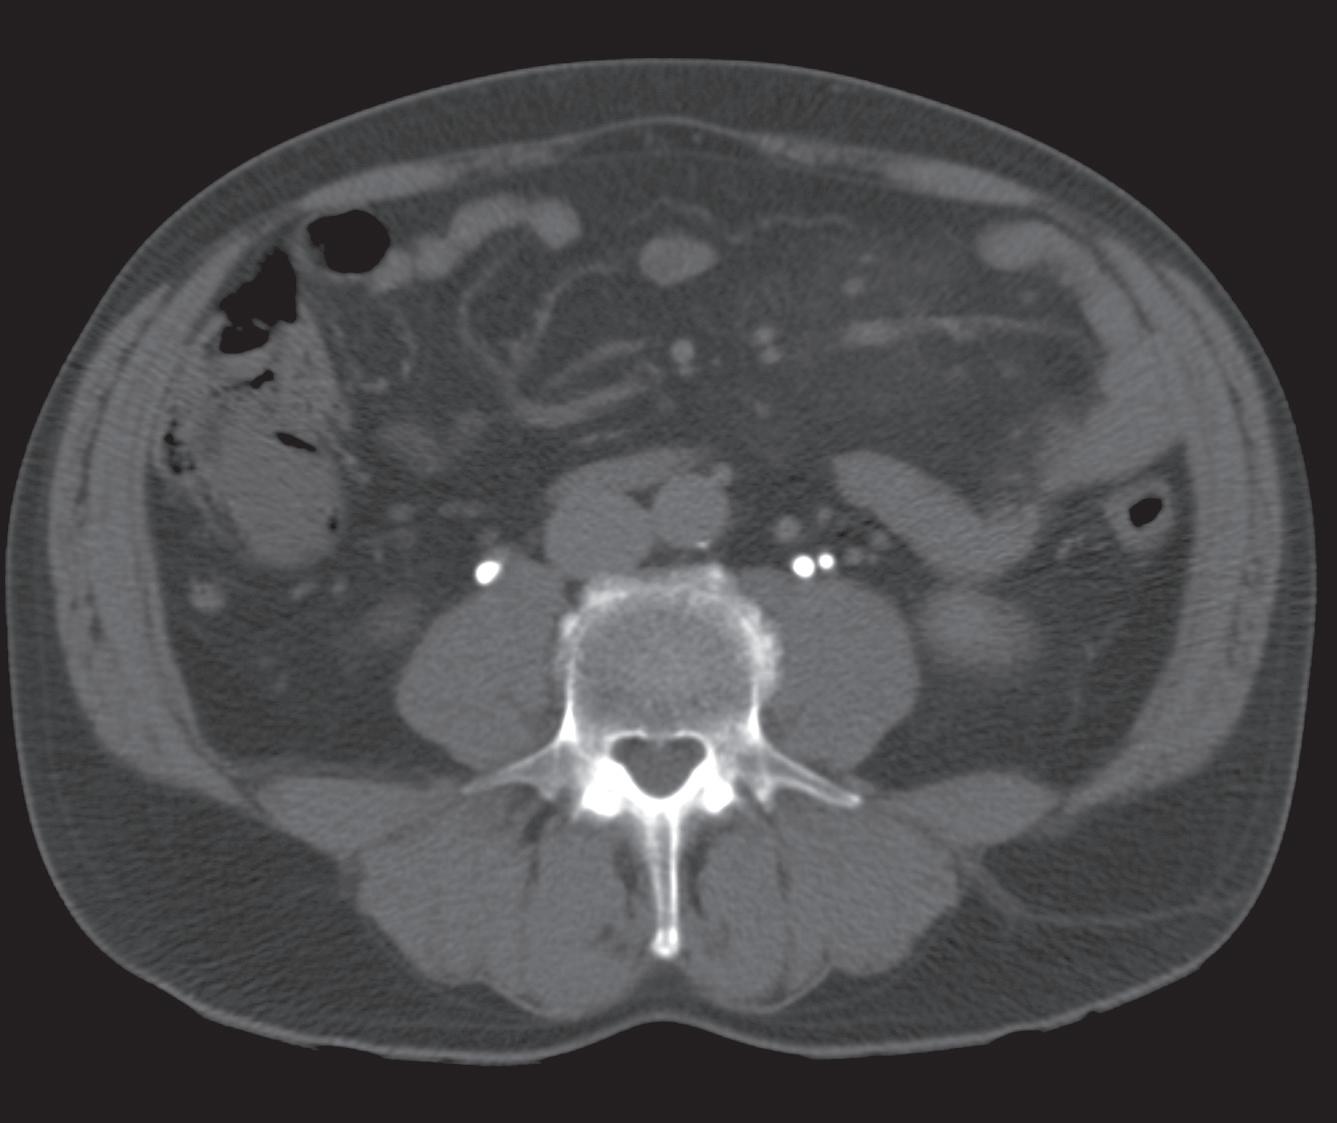

PH je jedn ou z nejčastějších a nejnáročnějších komplikací spojených s vytvořením stomie, vč. ileálního konduitu (obr. 1 a 2). Je definována jako protruze břišních orgánů skrze defekt v břišní stěně v bezprostřední blízkosti stomie [3]. Výskyt PH se u pacientů s ileálním konduitem pohybuje dle literatury v širokém rozmezí 10– 65 %, přičemž až 30 % z nich může vyžadovat chirurgickou intervenci kvůli bolestem, únikům moči, obtížím s lepením stomického sáčku nebo zánětům a podráždění kůže [4,5].

Obr. 1. Pacient s parastomální hernií po otevřené radikální cystektomii s použitím ileálního konduitu.

Fig. 1. Patient with parastomal hernia following open radical cystectomy with ileal conduit.

Obr. 2. Nález na počítačové tomografii u pacienta s parastomální hernií po otevřené radikální cystektomii s použitím ileálního konduitu.

Fig. 2. Computed tomography finding in a patient with parastomal hernia following open radical cystectomy with ileal conduit.